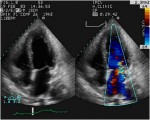

Immagine112-109x150.jpg Immagine122-150x120.jpg

Insufficienza mitralica di tipo IIIa, dovuta a limitazione dei movimenti dei lembi durante la diastole.